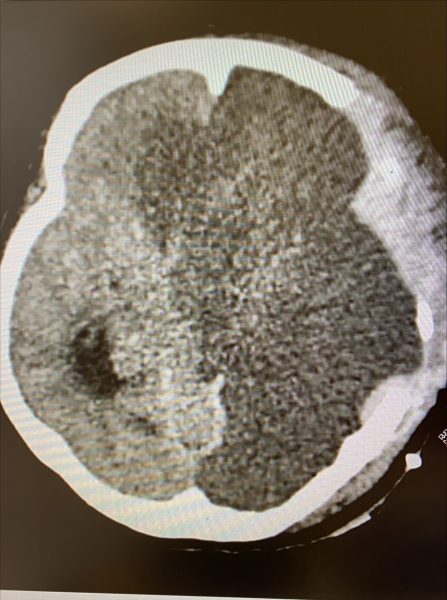

检查后,我发现她的颈动脉栓塞,也就是房颤形成的血块堵塞了颈动脉,令血液无法送达大脑,进而造成半个脑部出现严重的缺血性中风,因为缺血的范围极大,颅内压升高的情况也非常严重。

脑中风的治疗是分秒必争,如果确诊为缺血性中风且病发时间在3小时内,可以注射静脉血栓溶解剂,打通脑部血栓,减少脑组织的伤害。但房太因为延误送医,错过了黄金三小时,所以无法进行血栓溶解治疗。

但我们没有放弃抢救,脑神经外科医生第一时间为她做了紧急开颅手术,也就是把头骨打开减压,舒缓脑肿胀。